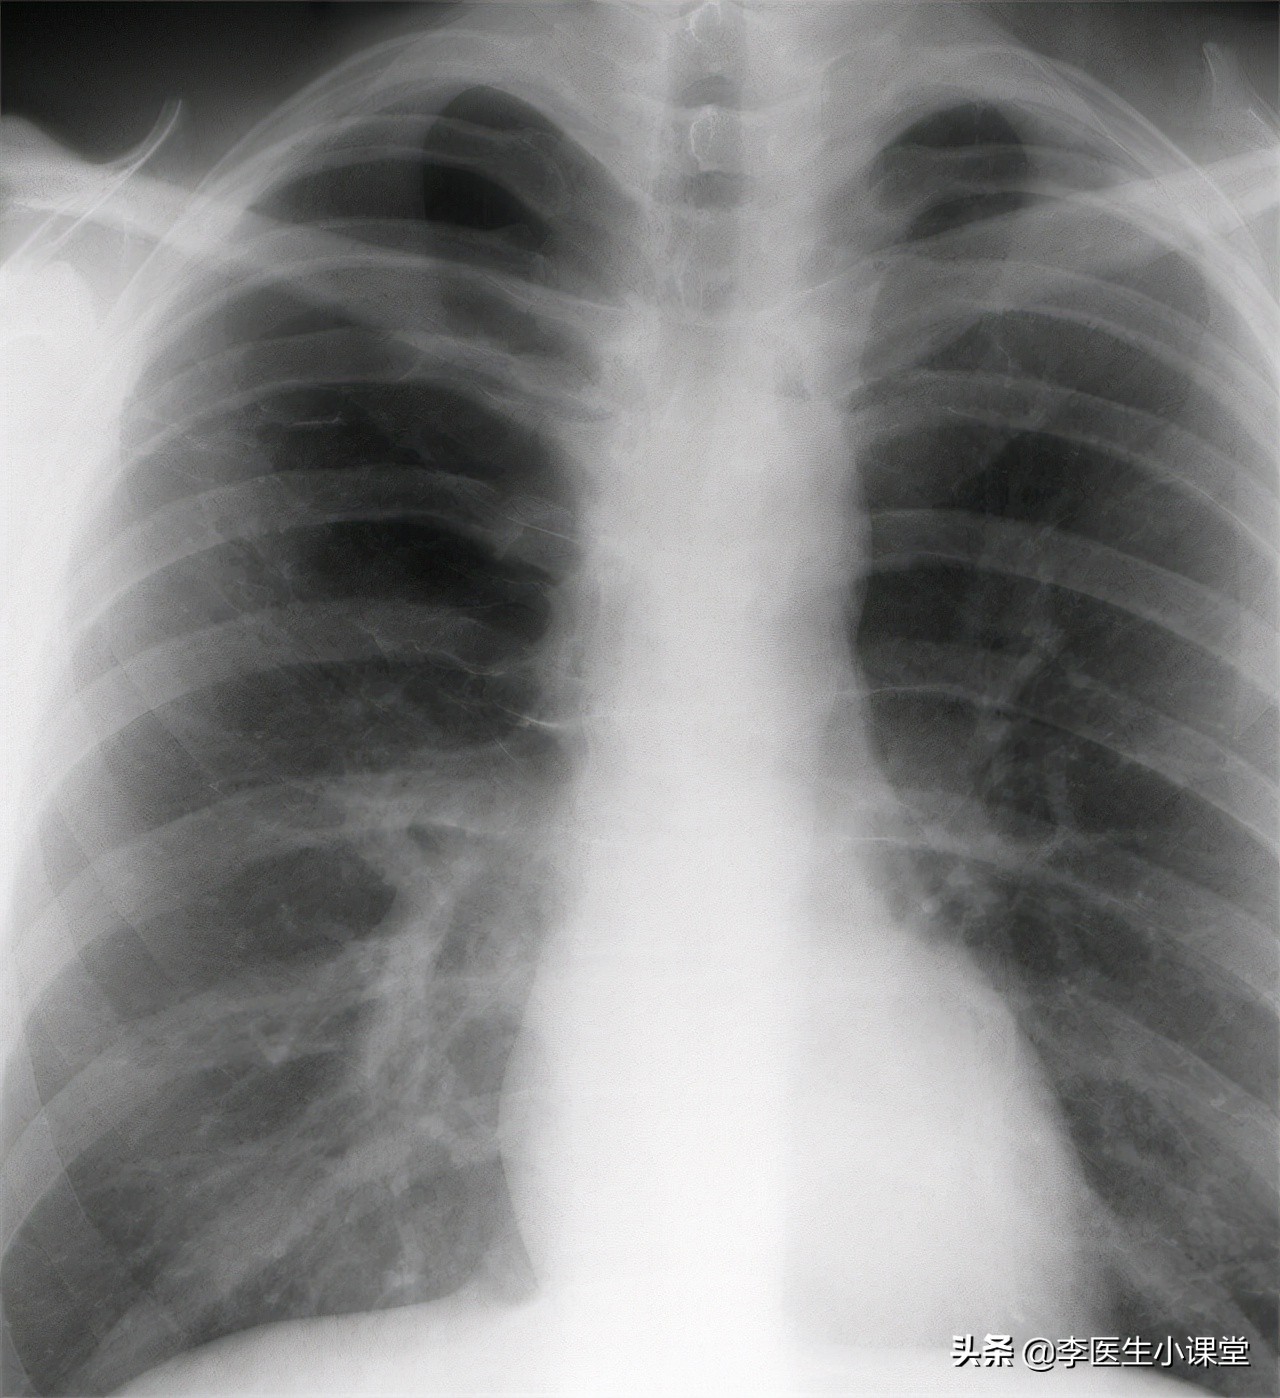

吸烟者的肺和不吸烟者的肺有着相当大的差异。 我们不吸烟人的肺颜色呈现出润红色,这是正常的颜色,而吸烟人的肺是所谓的“五彩肺”,那些常年吸烟,且吸烟量大的人的肺主要呈现黑色,这是因为*草烟**中的很多有毒有害物质残留在肺部,大量的有害物质聚*会集**造成中毒的症状,影响呼吸功能以及肺部的通气换气能力。

戒烟能够有效改善肺部的功能和形态。 如果一直吸烟,肺部就会一直受到尼古丁等有害物质的侵袭,肺部在不同沉淀物的影响下呈现出黑色,有一部分对身体的伤害是无法逆转的,但也有一些因吸烟带来的损害在戒烟后可以逐渐减少。吸烟造成的肺部纤毛减少,可以在戒烟大约三个月以后逐渐恢复,戒烟两到三个月以后,受损的肺部组织也会慢慢恢复到正常的状态,肺部的神经系统和血管也能得到修复,聚集在体内的毒素可通过咳出浓痰等形式排出体外,此时已经变黑的肺在一定程度上颜色改变。长期吸烟的人经常会感觉到呼吸困难,有时会有急喘、呼吸不畅等症状,这也是因为吸烟对肺部造成了损害,而肺部又和呼吸系统密切相关,戒烟后阻碍肺部正常流通的障碍物被去除,能够减轻呼吸不畅的症状。

总之,肺部一旦变黑就不会再恢复到原来的状态,即便是彻底的戒烟,也不能让已经变黑的肺部变白,但戒烟能够最大限度的改善肺部的状态,恢复肺部的功能,延长寿命。